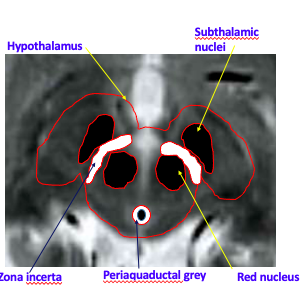

Brain regions for DBS

Which areas of the brain targeted for tremor? [3]

Which areas of the brain targeted for Dystonia? [1]

A

Tremor:

* Zona incerta

* Subthalamic nucleus

* GPin

Dystonia: